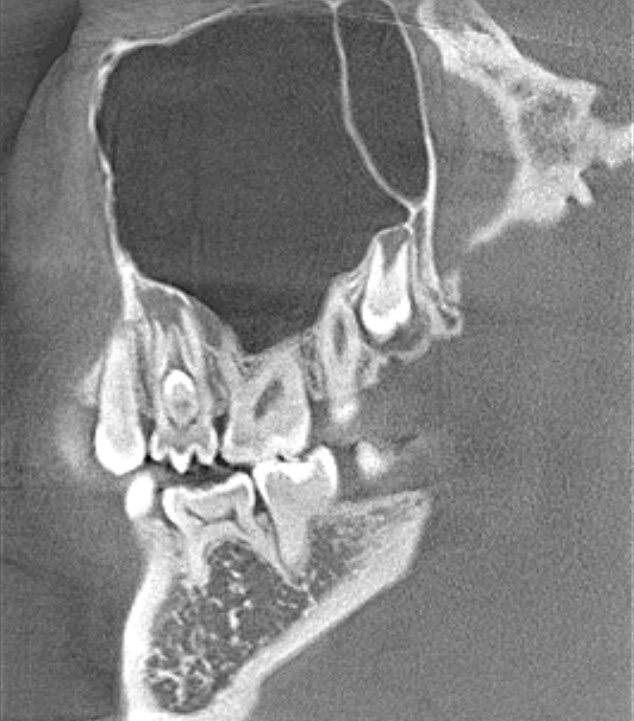

Вы слышали когда нибудь про "беременные зубы" ? А они реально существуют 😅 Называется такой дефект развития ❗️dens invaginatus ❗️или зуб в зубе. Такое происходит из за того, что коронковая часть зачатка зуба еще до того, как он прошел кальцификацию, совершает инвагинационное выпячивание внутрь самой себя. Впервые вышеозначенная аномалия была выявлена в 1794 году в зубах китов, у человека же подобный диагноз дебютировал в 1856 году. Встречаемость в популяции, по данным различных исследователей, от 0,5 до 13%. Боковые резцы верхней челюсти — 5%; Центральные резцы верхней челюсти — 8%; Премоляры нижней челюсти — 6%; Мезиоденс (сверхкомплектный зуб между центральными резцами) — 9%; Клыки верхней и нижней челюсти — 6%. На самом деле встречается очень и очень редко, и поговорив со своими коллегами, многие из них про это только в учебниках читали🎓 Но мне посчастливилось встретиться с таким диагнозом уже второй раз😎 Как правило пациент не подозревает об этом и это случайная находка на КЛКТ

Такое происходит из за того, что коронковая часть зачатка зуба еще до того, как он прошел кальцификацию, совершает инвагинационное выпячивание внутрь самой себя.

Как правило пациент не подозревает об этом и это случайная находка на КЛКТ, либо обращается с болью...

А дальше в зависимости от локализации такой "находки" выбирается подходящий план лечения!